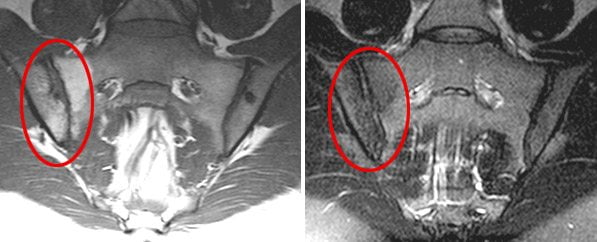

Рентгенологические признаки появляются на поздних стадиях сакроилеита, причем далеко не при всех его видах. Рентген-диагностика не позволяет вовремя выявить болезнь и своевременно начать лечение. Однако диагностировать заболевание на начальных этапах развития можно с помощью других, более современных методов исследования. Ранние признаки сакроилеита лучше всего видны на МРТ.

Наличие достоверных рентгенологических признаков поражения крестцово-подвздошного сустава позволяет поставить диагноз «сакроилеит». При отсутствии четких изменений на рентгенограммах больным рекомендуется определение статуса HLA-B27 и применение более чувствительных визуализирующих методов исследования (КТ, МРТ).

Магнитно-резонансная томография (МРТ) наиболее информативна в диагностике сакроилеита на самых ранних стадиях. Она позволяет выявить первые признаки воспалительного процесса в суставе – жидкость в суставной полости и субхондральный отек костного мозга. Эти изменения не визуализуются на компьютерных томограммах (КТ).

Компьютерная томография более информативна на поздних стадиях сакроилеита. КТ выявляет костные дефекты, трещины, склеротические изменения, сужение или расширение суставной щели. Но компьютерная томография практически бесполезна в ранней диагностике сакроилеита.